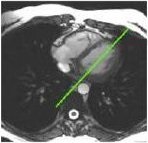

3. From the 4-chamber view, prescribe (red line indicates graphic location) and acquire a short axis view.

Figure 3. Prescribe short axis view